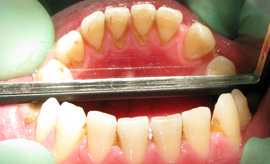

PARODONTOLOGIJA-ZDRAVLJENJE DLESNI ![]()

Parodontalna bolezen prizadene praktično vso populacijo, a ker poteka predvsem neboleče in počasi se njene posledice pacienti pogosto ne zavedajo. Poglavitni vzrok so bakterije in njihovi produkti v zobnih oblogah in zobnem kamenu. Prve spremembe se pojavijo na dlesnih, ki so krvaveče in otečene. Tekom let pa so prizadete tudi druge obzobne stukture, ki postopno propadajo, kar pacienti opazijo v obliki majajočih zob in umiku dleseni. Pacienti se pogosto s to težavo prepozno oglasijo v zobni ambulanti. Ključ uspeha zdravljenja je v poznavanju narave bolezni, zato je prvenstven natančen poduk pravilne ustne higiene pacienta in njegova motivacija in sodelovanje.

V večji meri prispevajo k nastanku bolezni pedvsem dejavniki na katere ljudje vplivamo sami: higiena, kajenje in stres. Diagnozo postavimo s pomočjo kliničnega pregleda, pri katerem ponavadi ugotovimo prisotnost zobnih oblog. Zobni kamen lahko vidimo ali ga zatipamo s sondami pod nivojem dlesni. Krvaveča dlesen na dotik govori o stalni prisotnosti mehkega zobnega plaka, v katerem je polno bakterij, ki povzročajo vnetje dlesni. Rentgenski posnetki so osnova za diagnostiko bolezni. Nudijo nam podatke o količini izgubljene alveolarne kosti (kost, ki obdaja zobne korenine) , kar je ključno za določitev resnosti in težavnosti bolezni. Količino izgubljene kosti in globino obzobnih žepov izmerimo s posebnimi merilnimi parodontalnimi sondami. Globina obzobnih žepov je glavni podatek, ki narekuje način terapije in prognozo bolezni.

Zdravljenje bolezni zajema predvsem ukrepe, ki zmanjšujejo ali odstranjujejo bolezenske dejavnike na katere lahko vplivamo tudi sami. V prvi vrsti se morajo pacienti zavedati pomena ustne higiene, nevarnosti kajenja in pomena stresnega življenja. Vzpostavitev in vzdrževanje ustrezne ustne higiene, ki vključuje uporabo medzobnih krtačk, medzobnih nitk, električnih krtačk, je bistvenega pomena za zdravljenje parodontalne bolezni. Terapija bi bila brez upoštevanja navodil za higieno popolnoma neuspešna. Ko pacienti razumejo in tudi izvajajo prvo fazo zdravljenja, torej pouk o higieni, lahko nadaljujemo terapijo. Cilj je odstranitev zobnega plaka in kamna, ki ga pacienti sami ne morejo odstraniti.

Opisane postopke izvajamo z ročnimi ali strojnimi inštrumenti. Če je potrebno se napoti pacienta k specialistu parodontologu v nadaljno obravnavo. Cilj terapij je zmanjšati globino obzobnih žepov in zmanjšati majavost zob. Sodelovanje pacienta v smislu upoštevanja navodil o ustni higieni in strokovno delo sta zagotovilo za uspeh.